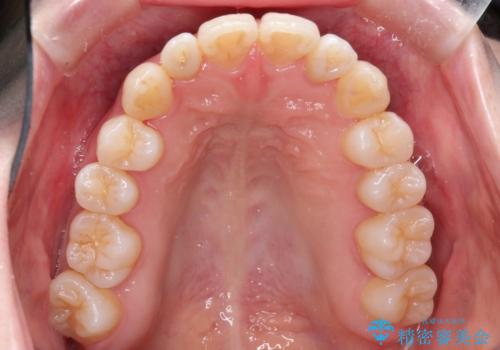

インビザラインで八重歯の矯正

- 八重歯を治したいとのことで、来院されました。

インビザラインにて、上顎の歯と歯の間をわずかに削り、並べる計画としました。

使用時間を守っていただけたので、比較的スムーズに矯正を終了することができました。